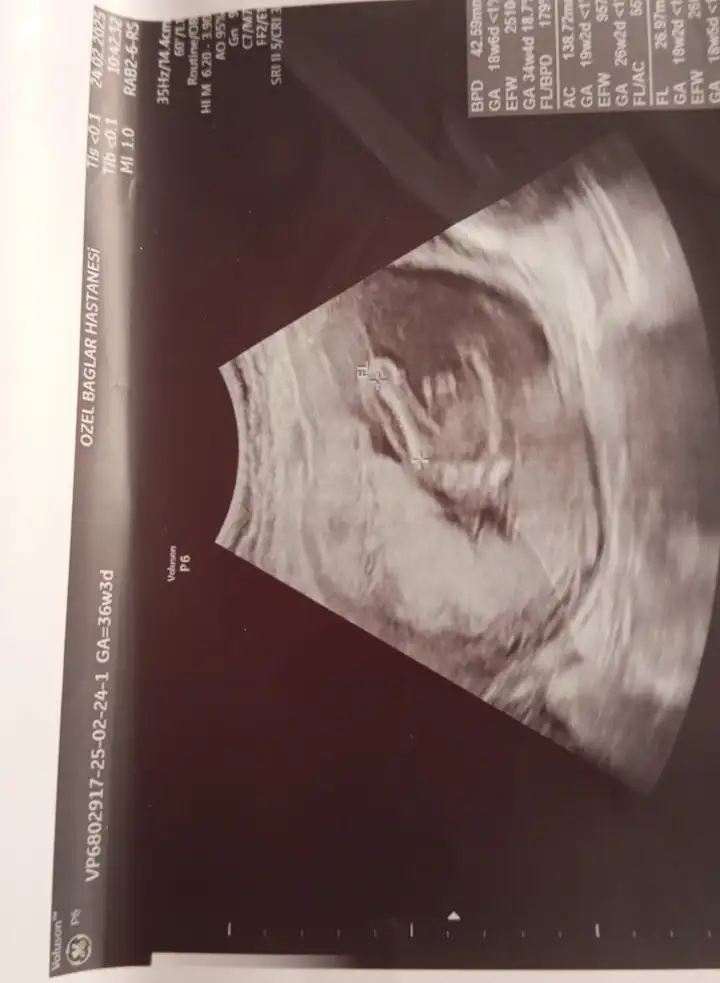

Bunlarada bakar mısınız

Eklentiler

• IMG_20250224_153214.webp

IMG_20250224_153214.webp

19,2 KB · Görüntüleme: 54

• IMG_20250407_163039_632.webp

IMG_20250407_163039_632.webp

21,7 KB · Görüntüleme: 39